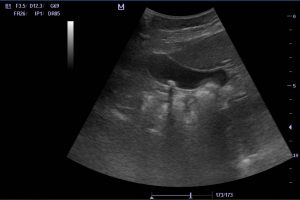

Diplomados en Ultrasonografía